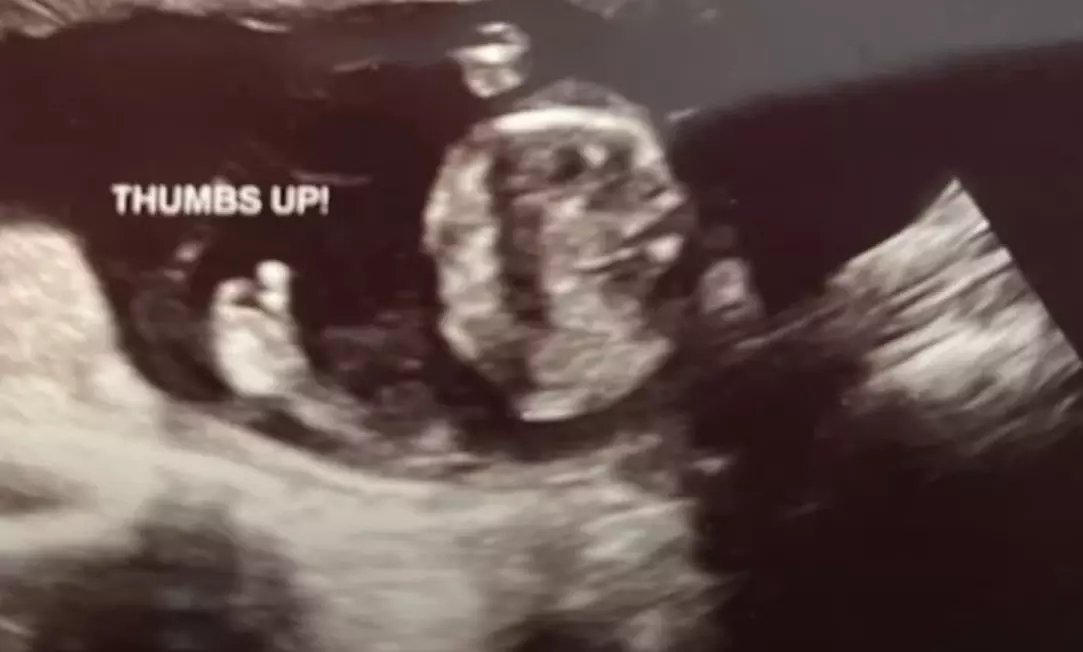

Ultrasound technician Lauren Purtee was not having the best day at Pregnancy Center East in Cincinnati, Ohio, earlier this fall. She had done several scans, and some were more difficult than others. It was the last scan of the day in which the baby on the screen spoke for him or herself, indicating that all would be okay. The baby gave a literal thumbs-up just at the right time.

“I had just hovered over the hand of the baby when it just popped up. It gave a thumbs up,” she said. “Everybody in the room was smiling and giggling.”

The mood was lifted for the staff at that very moment, Purtee said.

Purtee said the thumbs up felt like a sign from God that the center is doing the right things. “It’s like He was telling us it will be okay.”